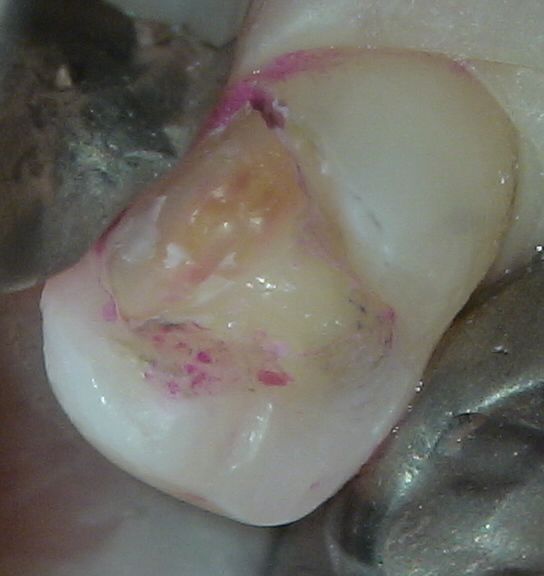

虫歯を完全に取り除けているとは言えない治療が多くみられることは非常に問題です。わかりずらいと思いますが、本当に虫歯を取り除くこと自体が技術であり、それが出来なければ、虫歯の再発が起こり、治療の意味がなくなります。

このような症例にいくら顕微鏡を使っても虫歯を取り残して治療が終わってしまっては、結果はよくありません。

また当医院では強酸性水をユニットに流しているために、虫歯を削った部分を洗浄すると、非常に殺菌効果が高いため、確実な消毒ができ、また治療中に万が一神経が出てしまっても、神経を救える確率が高いのです。(水道水をユニットに流している場合は治療中に感染する可能性があり、ここまで経過はよくない)

また、レジンは吸水性あるため、MTAの上に詰める材料としてはあまり適当ではありません(グラスアイオノマーの方が経過が良い気がします)。ちなみに虫歯を残したままMTAを詰めたり、レジンを詰めたりすると数年後に虫歯が大爆発していることがあります。しかも厄介なことに痛みはほとんどありません。